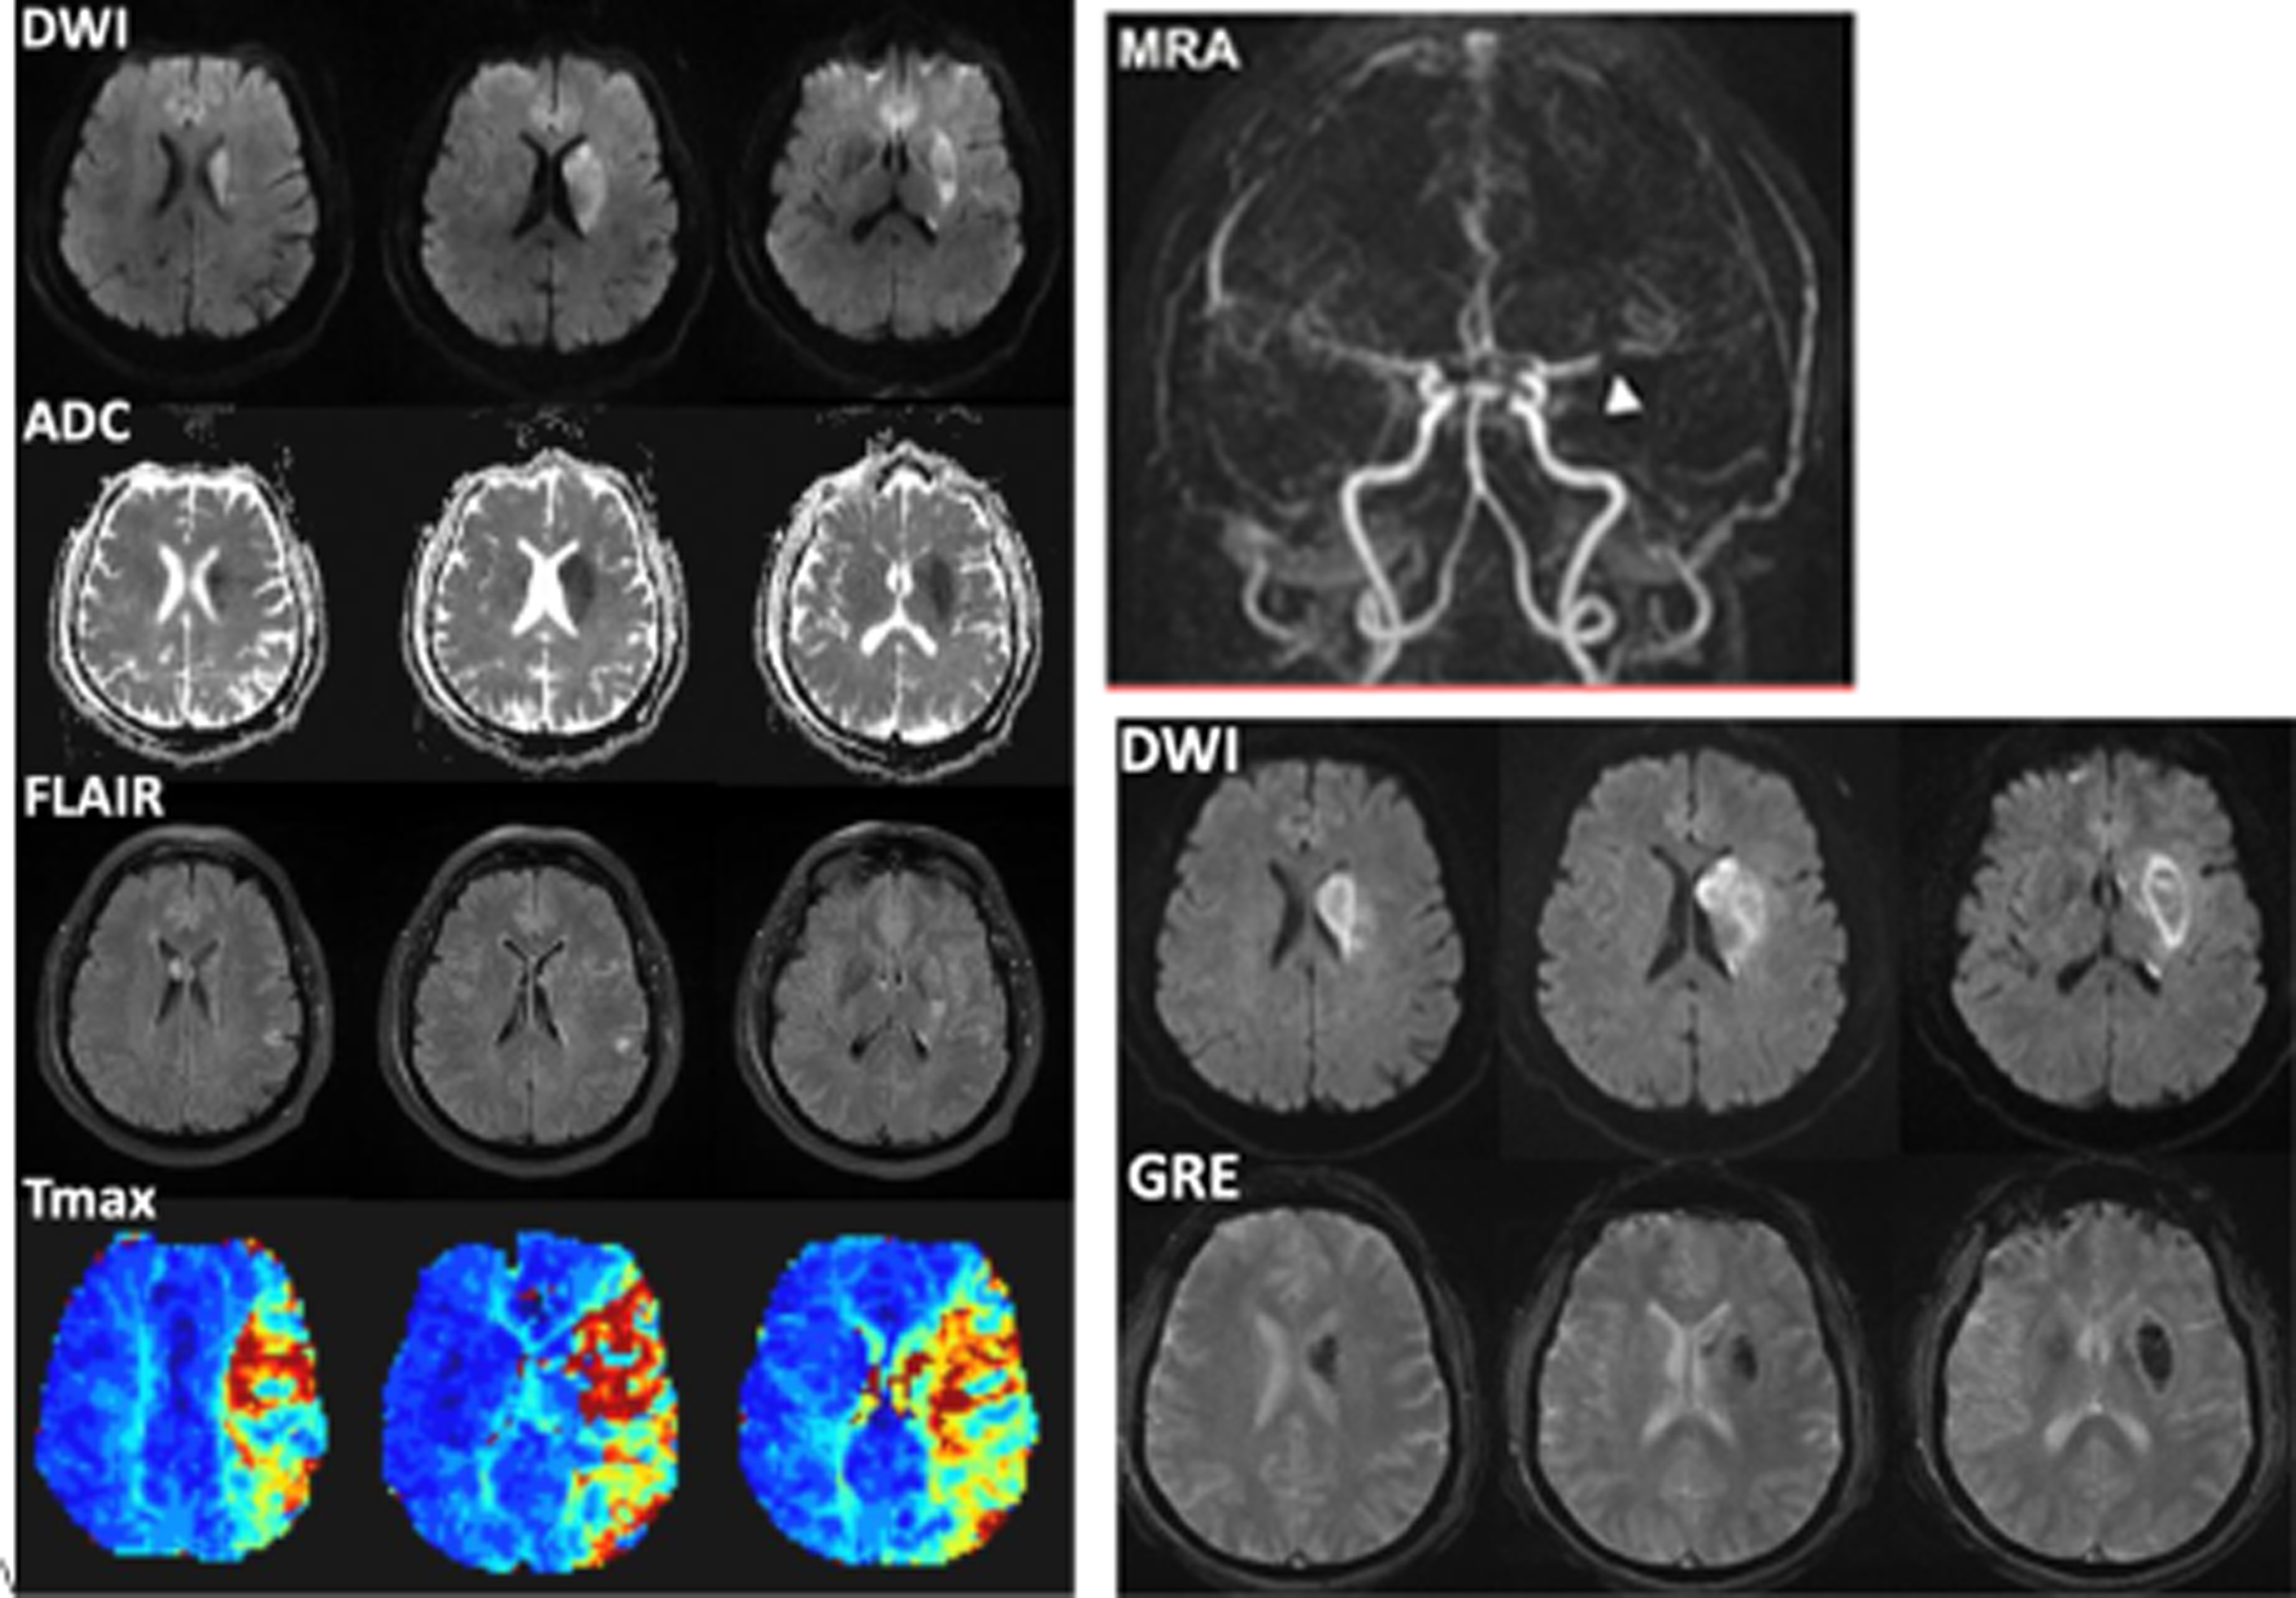

Imaging Stroke Patients with Unclear Onset Times Radiology Key Old Stroke Radiology Hyperacute (less than 12 hours), acute (12 to 24 hours), subacute (24 hours to 5 days), and old (within weeks after stroke). In this first article, we review various imaging modalities that are utilized to diagnose acute ischemic stroke. The second part, appearing in the november/december 2021 issue. Use of various mr imaging sequences in dating ischemic stroke is discussed,. Old Stroke Radiology.

Acute Ischemic Stroke Neuroimaging Clinics Old Stroke Radiology The goal of imaging in a patient with acute stroke is: The key to interpreting ct perfusion in the setting of acute ischemic stroke is understanding and identifying the infarct core and. Ncct findings in ischemic stroke depend on the age of infarction: Unenhanced ct can be performed quickly, can help identify early signs of stroke, and can help rule. Old Stroke Radiology.

Acute Stroke Imaging Radiology Key Old Stroke Radiology In this first article, we review various imaging modalities that are utilized to diagnose acute ischemic stroke. The key to interpreting ct perfusion in the setting of acute ischemic stroke is understanding and identifying the infarct core and. Ncct findings in ischemic stroke depend on the age of infarction: Use of various mr imaging sequences in dating ischemic stroke is. Old Stroke Radiology.

Acute Stroke Imaging Radiology Key Old Stroke Radiology In this first article, we review various imaging modalities that are utilized to diagnose acute ischemic stroke. The second part, appearing in the november/december 2021 issue. The goal of imaging in a patient with acute stroke is: Exclude hemorrhage differentiate between irreversibly affected brain tissue and. Use of various mr imaging sequences in dating ischemic stroke is discussed, with a. Old Stroke Radiology.